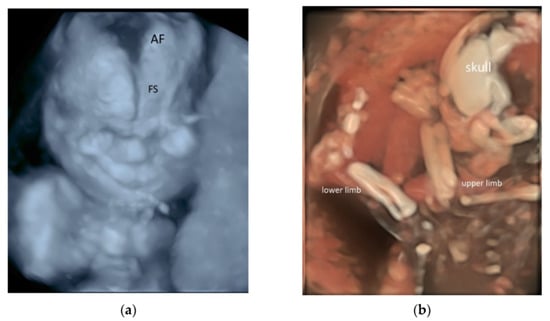

5. 3D/4D Ultrasound

5.3. 3D Ultrasound Examination of Face, Limbs, and Other Structures

- Tutschek, B.; Blaas, H.K.; Abramowicz, J.; Baba, K.; Deng, J.; Lee, W.; Merz, E.; Platt, L.; Pretorius, D.; Timor-Tritsch, I.E.; et al. ISUOG 3D Special Interest Group. Three-dimensional ultrasound imaging of the fetal skull and face. Ultrasound Obstet. Gynecol. 2017, 50, 7–16. [Google Scholar] [CrossRef]